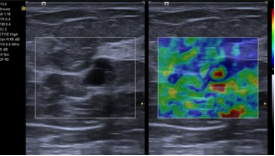

eSie Touch Elasticity Imaging(EI) 应变弹性成像: EI 应变弹性成像技术,用于浅表软组织病变的诊断,为临床提供敏感的高分辨率弹性成像,具备彩色和灰阶两种显示模式,并提供半定量工具:面积比、径线比、应变率比值。QF:不可或缺的质控指标,保证测值的准确性。